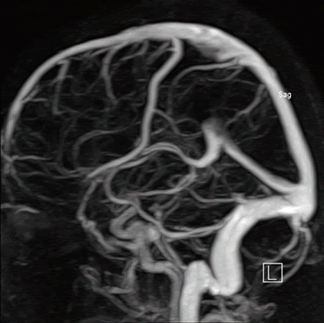

Диагностика магнитно-резонансная ангиография сосудов головного мозга производится при подозрении на тромбофлебит сигмовидного синуса.

Тромбоз сигмовидного синуса выявляется при:

- МРТ ангиографии сосудов головного мозга с контрастированием